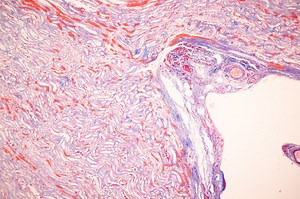

- Appendix

Anatomy - Appendix